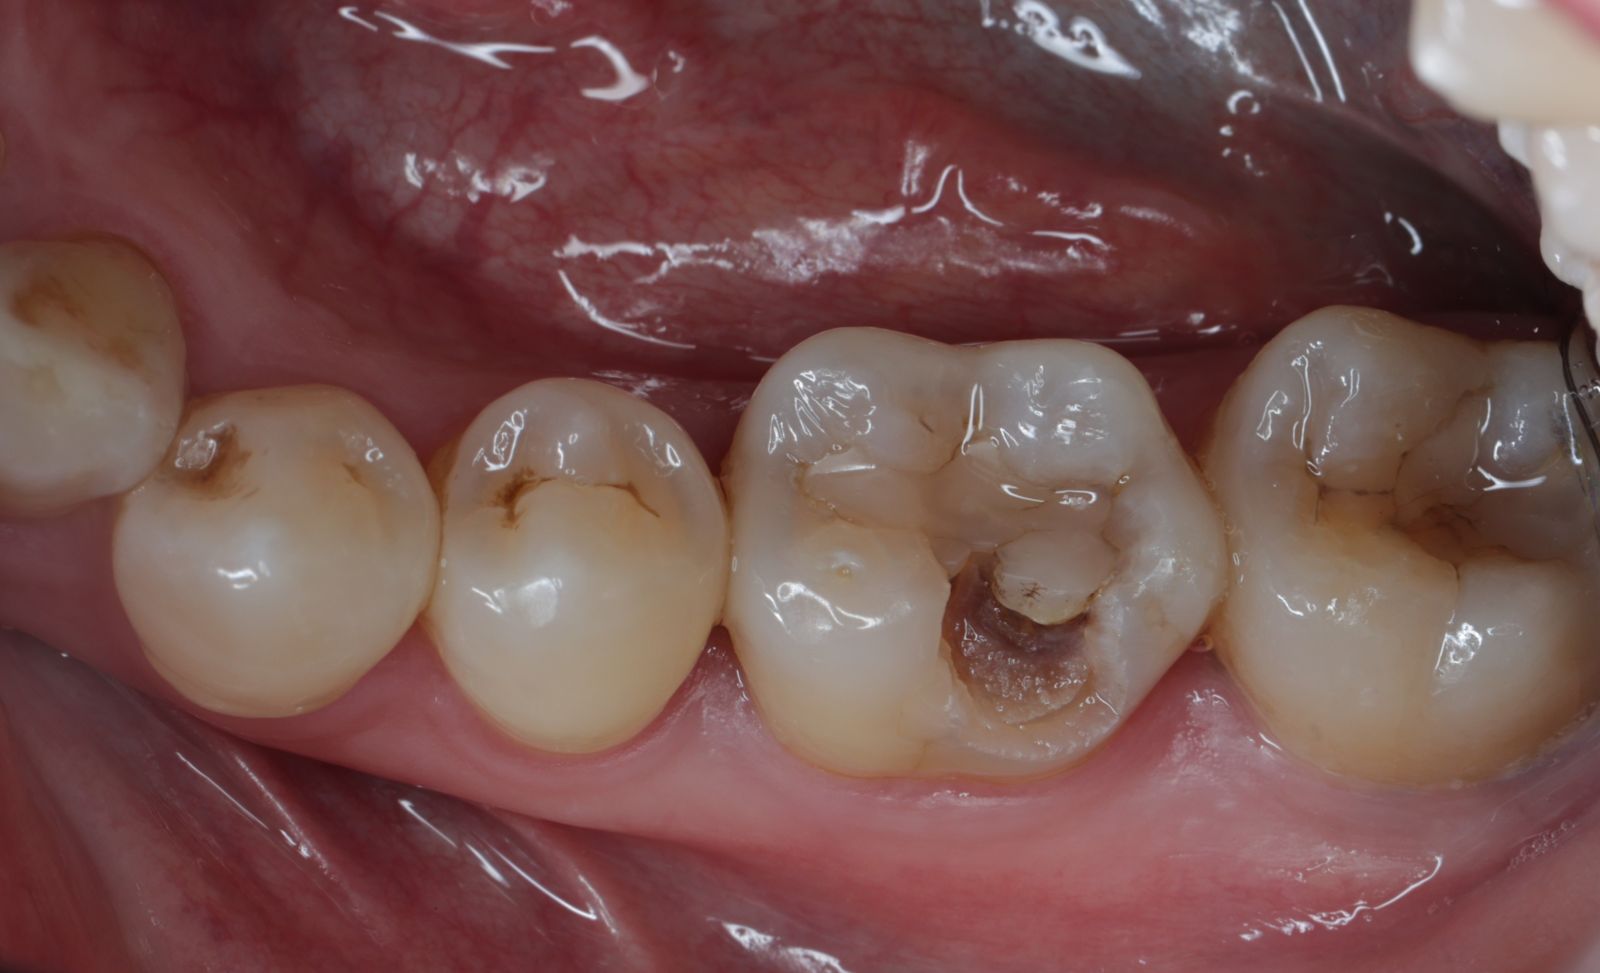

【 案 例 二 】